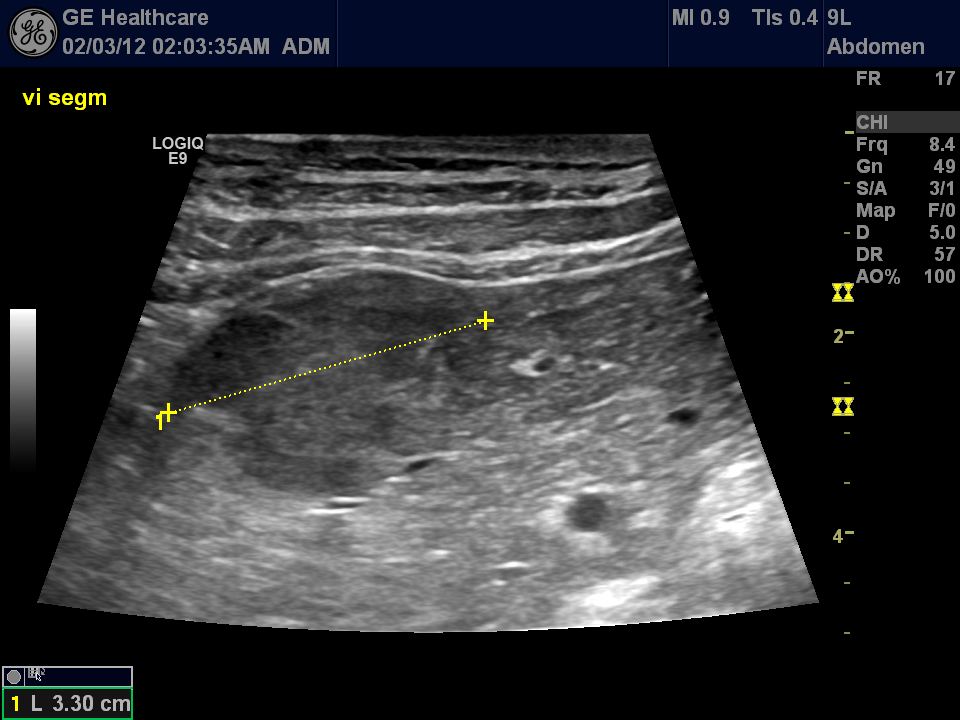

| Time-intensity-curves of to selected ROI (yellow – ring enhancement of the FLL, blue – normal liver parnchyma). Note the early enhancement of the metastases (time-to-peak). |